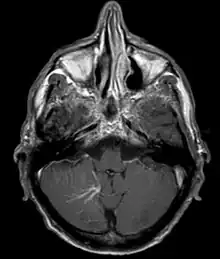

Developmental venous anomaly in the cerebellum seen on axial contrast-enhanced T1 weighted MRI

A developmental venous anomaly (DVA, formerly known as venous angioma) is a congenital variant of the cerebral venous drainage. On imaging it is seen as a number of small deep parenchymal veins converging toward a larger collecting vein.